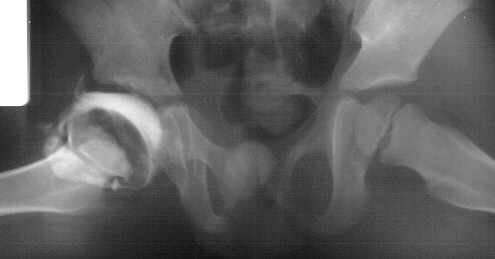

- Post Operative Day 18: R hip Xray: subluxation of R hip, possible metaphyseal

lucency consistent with osteomyelitis. Taken to OR for repeat I & D

of R hip via posterior approach with Penrose drains and hip spica cast

(15cc seropurulent fluid drained). Antibiotics changed to Oxacillin 225mg

IV q4.

Institute. Initial labs: WBC 15,100, ESR 72. R hip Xray: changes in proximal

. metaphysis including lucency and demineralization, hip subluxated. Treated

with oxacillin and Pavlik harness.

- 2 month Office Follow Up: Rt hip Xray: progressive destruction of capital

femoral epiphysis, cystic changes in metaphysis consistent with AVN.

This case is an example of untreated septic arthritis which caused avascular

necrosis of the proximal femur. The primary cause of this is undrained

septic hip. Repeated aspiration is not adequect treatment of a septic hip.